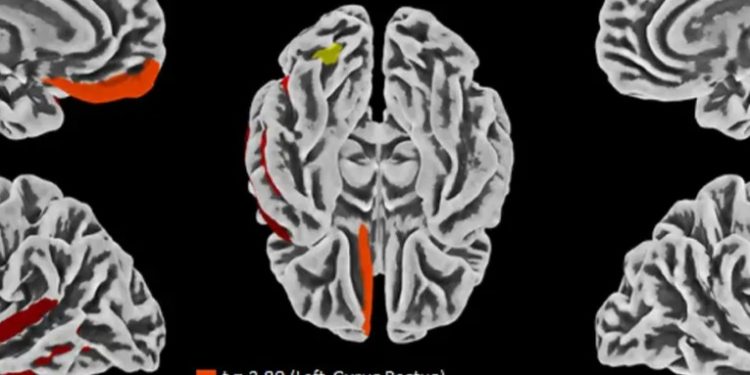

Según informó la Ponce Health Sciences University (PHSU), donde Ramos Benítez es catedrático, para el estudio se examinaron 44 fallecidos por COVID-19 y se realizó un análisis detallado del sistema nervioso central en 11 de estos para entender cómo se propaga el virus y en qué partes del cuerpo permanece.

«En algunos casos, encontramos que el virus seguía presente en varios órganos, incluido el cerebro, más de siete meses después de la aparición de los síntomas. Aunque el virus estaba en distintas áreas del cuerpo, observamos sorprendentemente poco daño o inflamación fuera de los pulmones», explicó Ramos Benítez.

Destacó que «esto sugiere que el COVID-19 puede persistir en diversas partes del cuerpo mucho después de la infección inicial, incluso sin causar daño directo en esos tejidos. Comprender dónde permanece el virus, podría ayudarnos a conocer mejor los efectos a largo plazo».